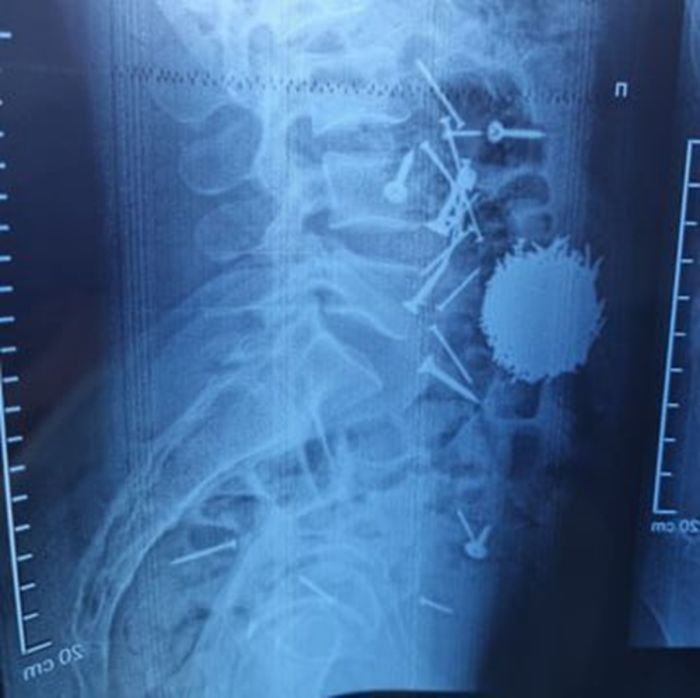

Молодой человек поступил в больницу с жалобами на сильную боль в животе. После проведения диагностических процедур медики были поражены: рентгеновские снимки показали наличие в желудке большого количества металлических предметов.

К счастью, врачи смогли оперативно оказать помощь. Хирургическое вмешательство, длившееся около часа, прошло успешно. Пациент находится под наблюдением специалистов, его состояние стабильно.